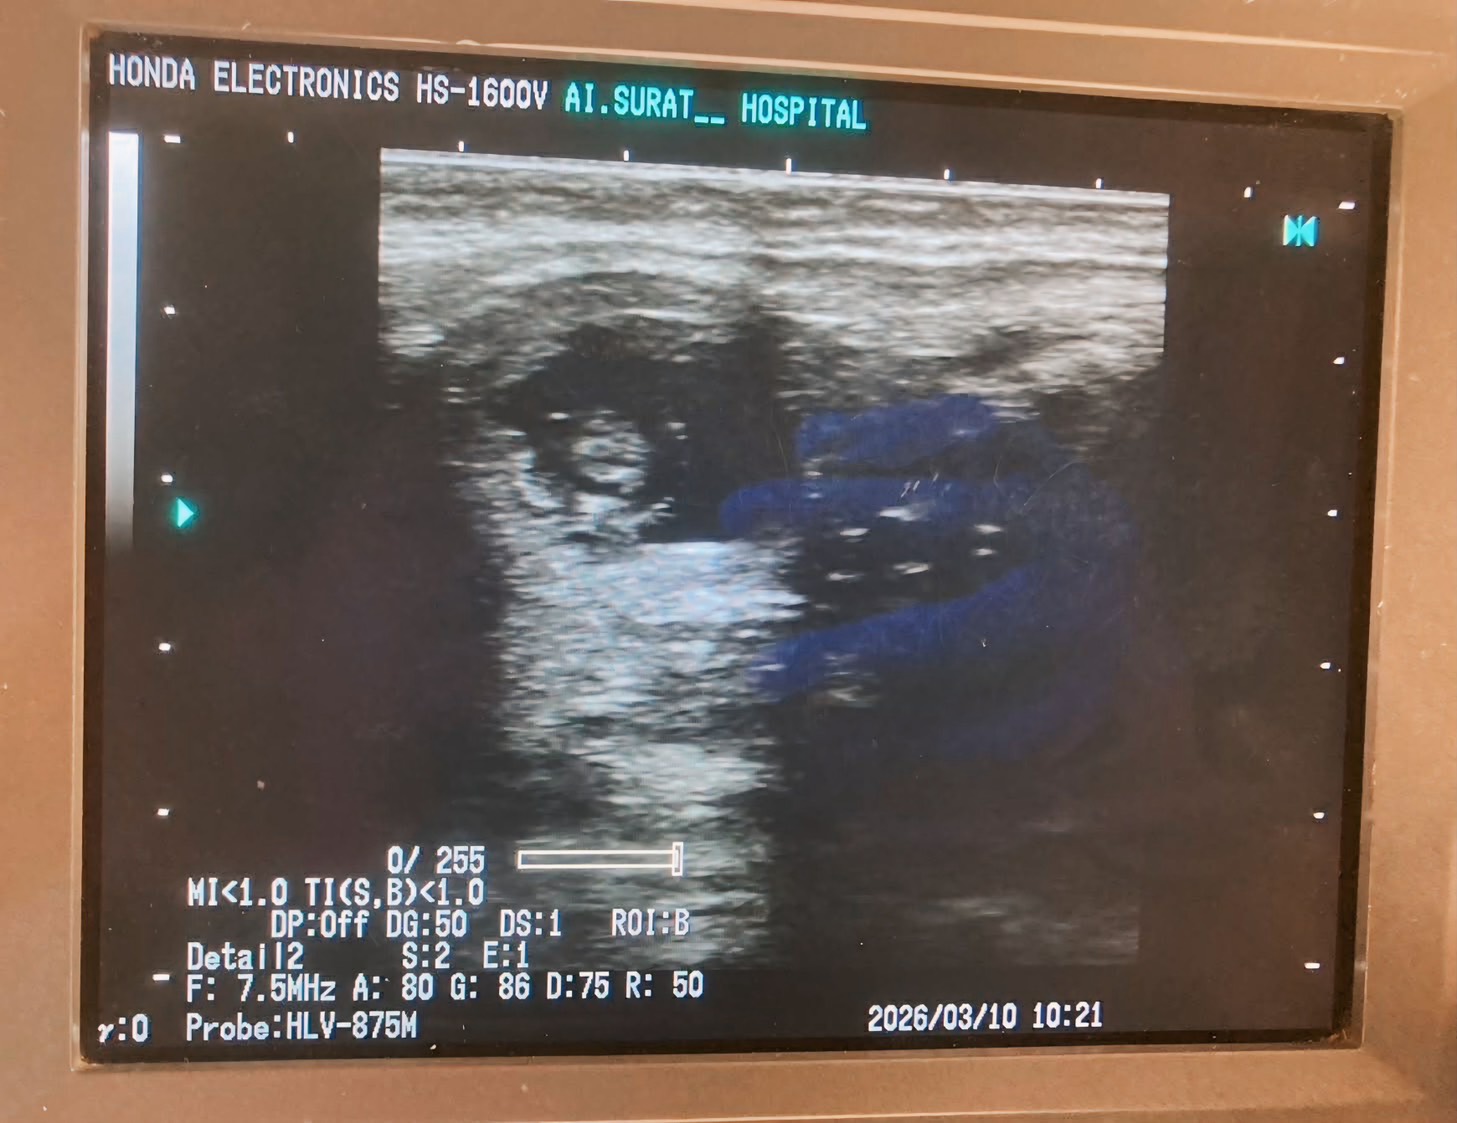

ล้วงตรวจท้องโค 4 ตัว ท้อง 4 ตัว

ตรวจระบบสืบพันธุ์ จำนวน 1 ตัว